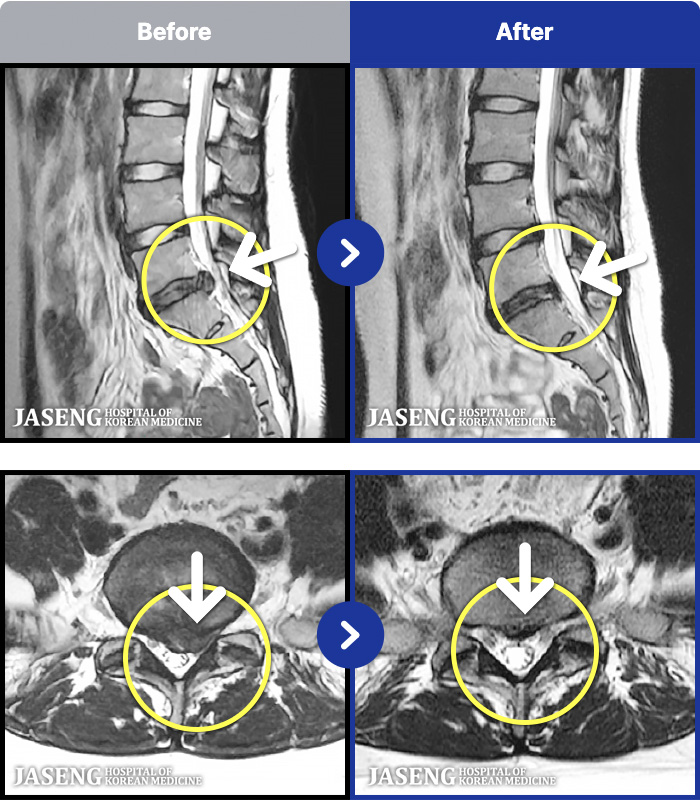

MRI ġ

1,301 MRI ũ ʸ Ȯϼ.